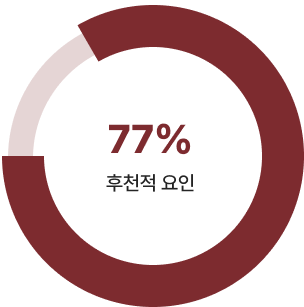

영양, 수면, 자세, 운동, 호르몬 등 다양한 후천적 요인을 종합적으로 관리할 때 비로소 성장 가능성이 열립니다.

유전적 요인 VS 후천적 요인

키를 결정짓는 요인은 유전 23%, 후천 77%

성장장애의 원인을 정확히 파악하고, 운동, 영양, 호르몬, 생활 환경을 종합적으로 관리해야 우리 아이가 몰라보게 자랄 수 있습니다.